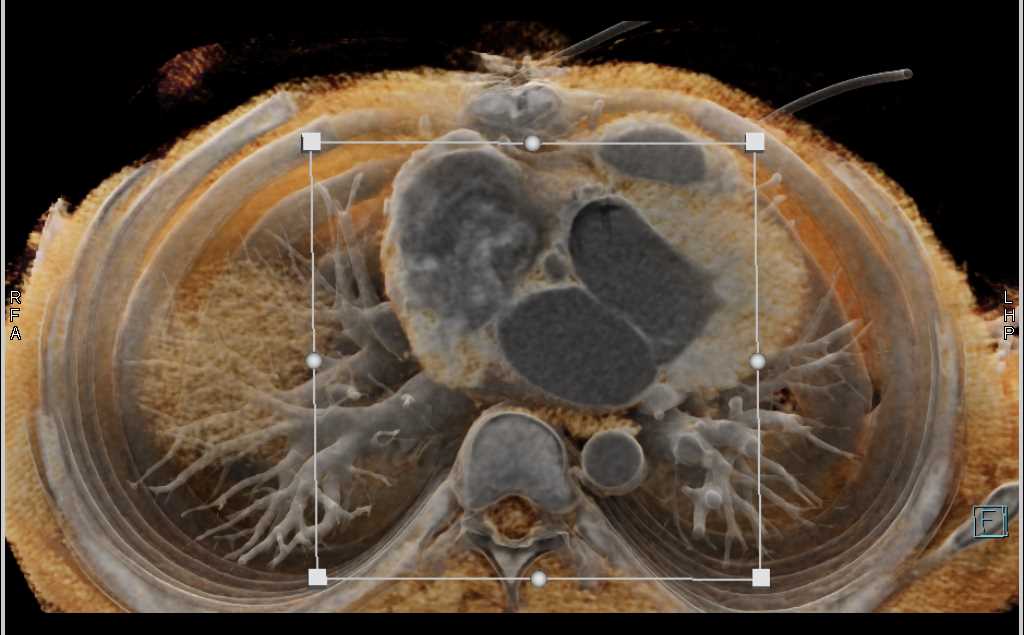

Diagnosis

Aortic Valve Repair